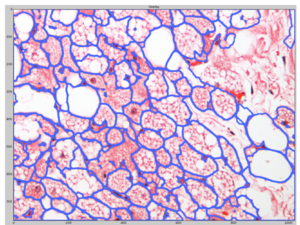

We then import the resulting probability map from ilastik into CellProfiler and use it to identify cells (marked by blue outlines):